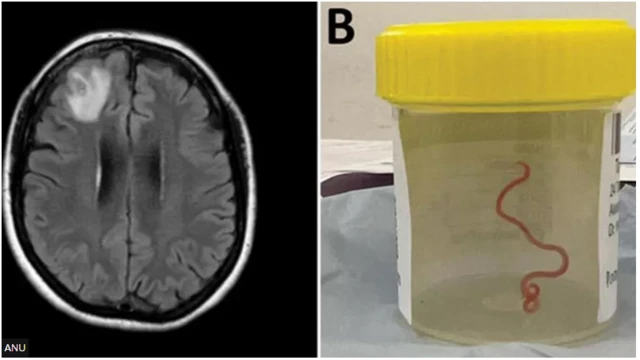

Fun igba akọkọ lagbaye, awọn onimọ sayẹnsi ti yọ aran to to iwọn sẹntimita mẹjo(8cm) laaye ninu ọpọlọ arabinrin kan lorilẹede Australia.

Aran ọhun ti awọn oloyinbo n pe ni Worm ni wọn yọ kuro ni iwaju ori arabinrin naa lasiko ti wọn se iṣẹ abẹ fun ni agbegbe Canberra, ni ọdun to kọja.

Aran ọpọlọ ti wọn pe orukọ rẹ ni Phidascaris robertsi ni o wọpọ laarin ejo nla, ti wọn ko tii ri iru rẹ lara eniyan ri, paapaa lara awọn ejo ni wọn wọpọ ni agbegbe Australia.

Ọdun 2021 ni arabinrin naa ni wọn be lọ si ileewosan ni ọdun 2021, ti wọn si pe nkan wa ni iwaju ọpọlọ rẹ.

Amọ asiko ti wọn n se isẹ abẹ fun ni ọdun 2022 ni ọbẹ dokita naa kan nkan aramanda to n rin ni ọpọlọ rẹ naa.